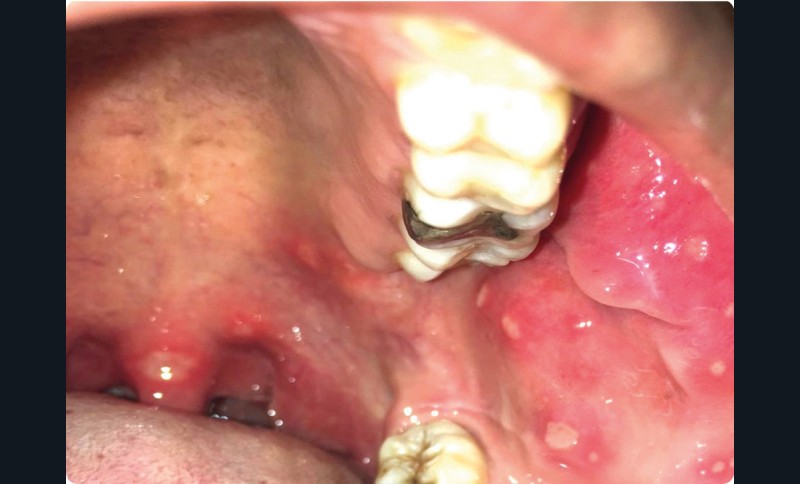

• On observait au niveau endo-buccal de nombreuses lésions typiques d’aphtes d’aspect milliaire ou vulgaire, sur la joue, le palais mou et la luette.